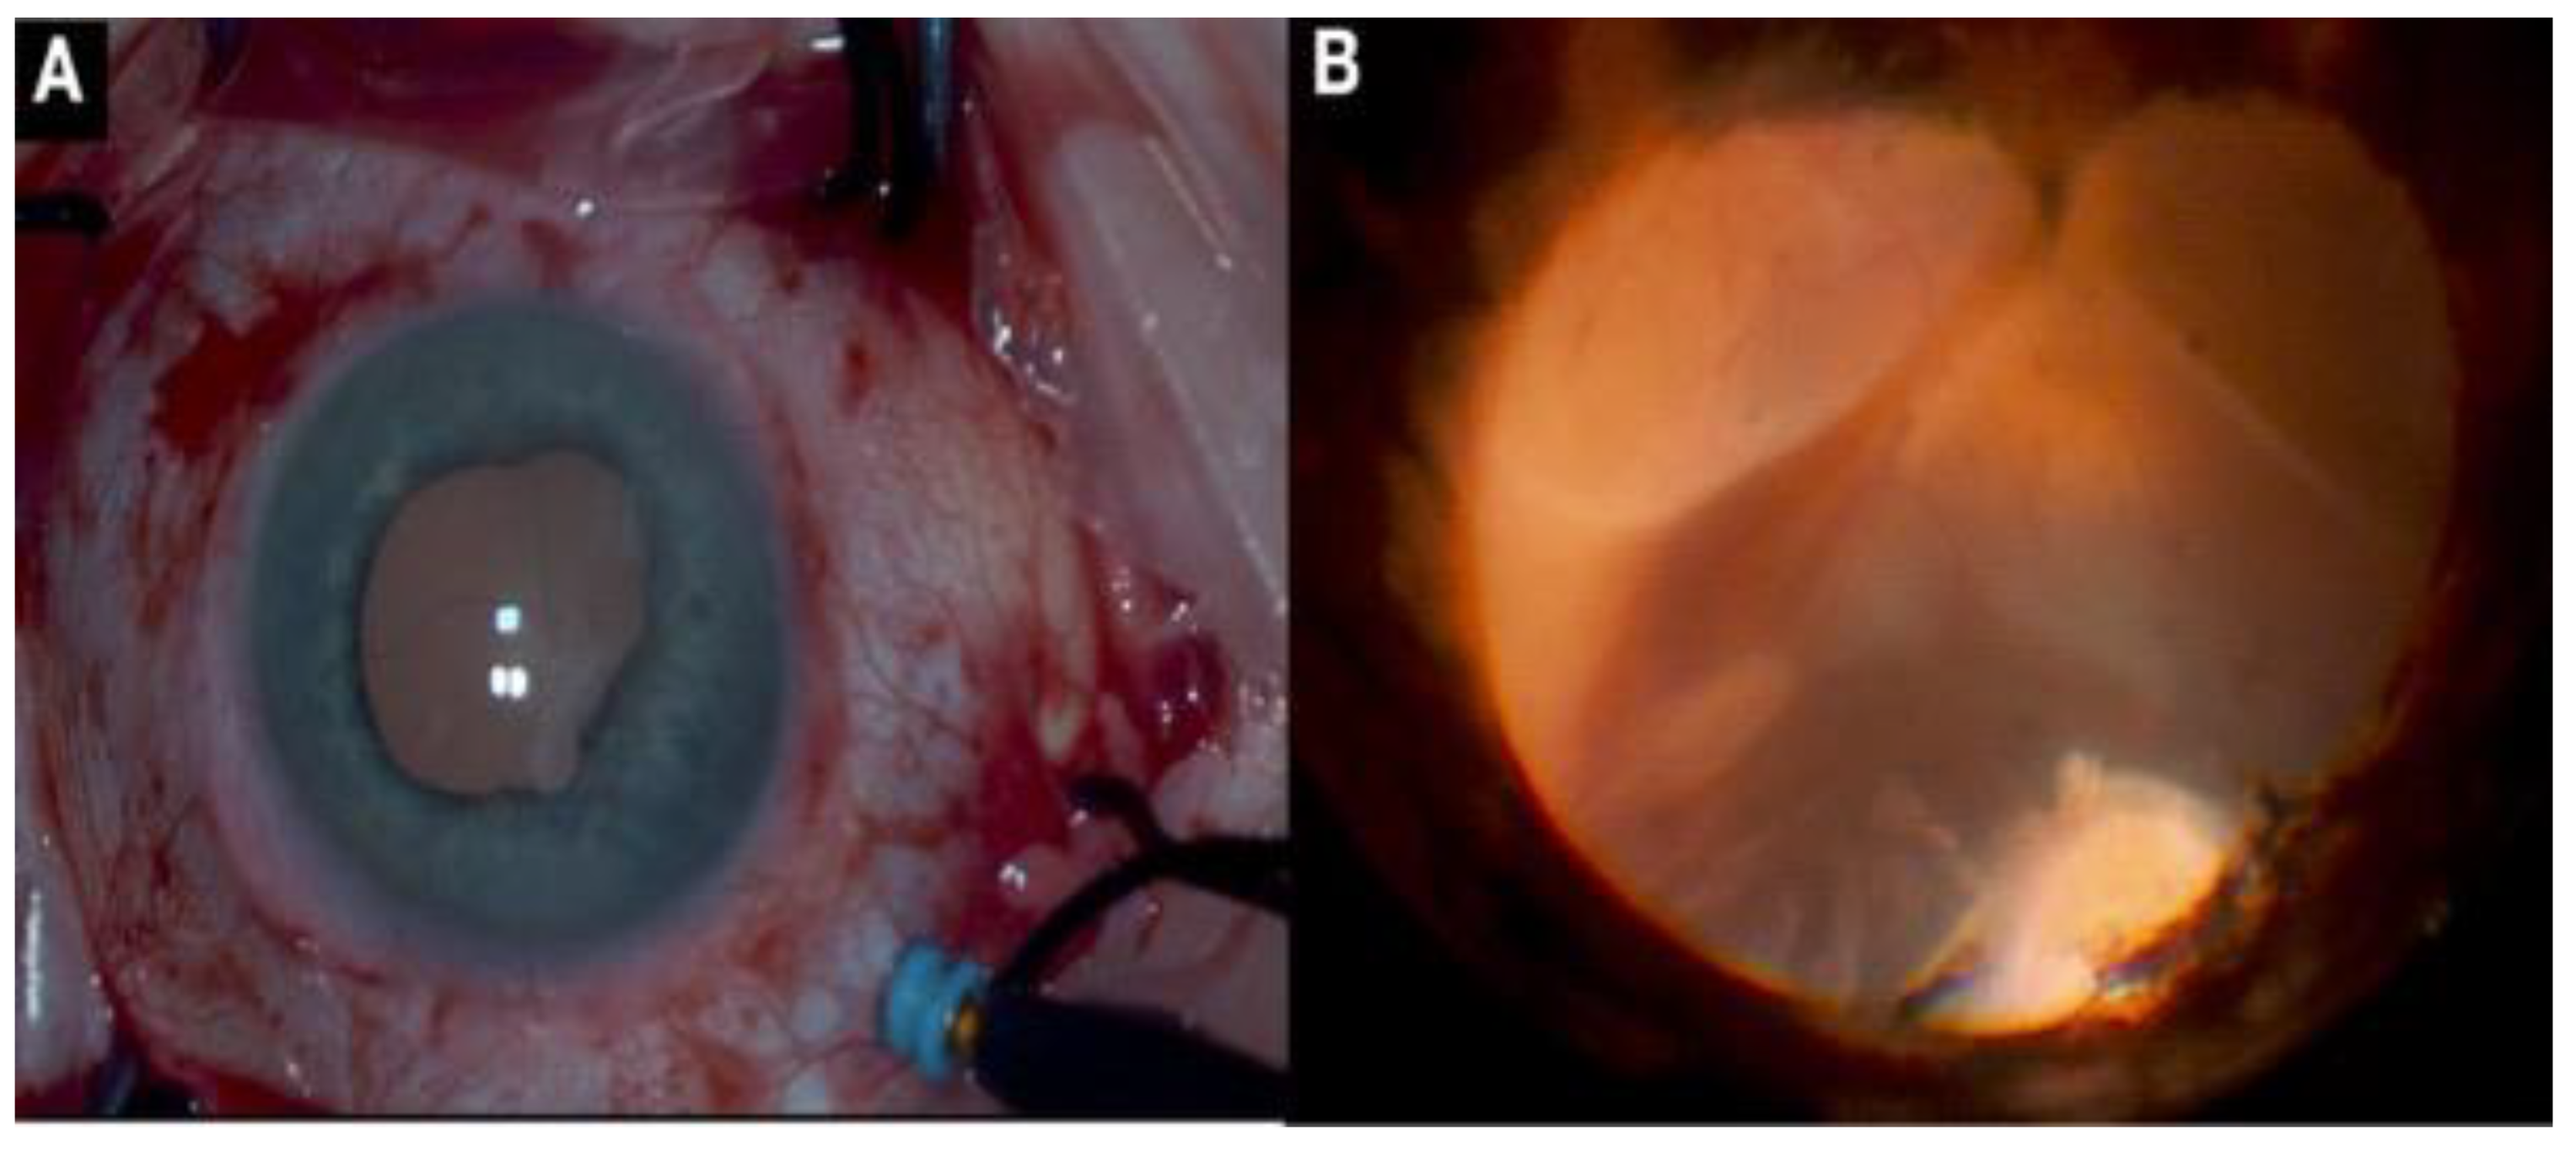

2.7. Intraoperative OCT

2.10. Endoscopic Surgery